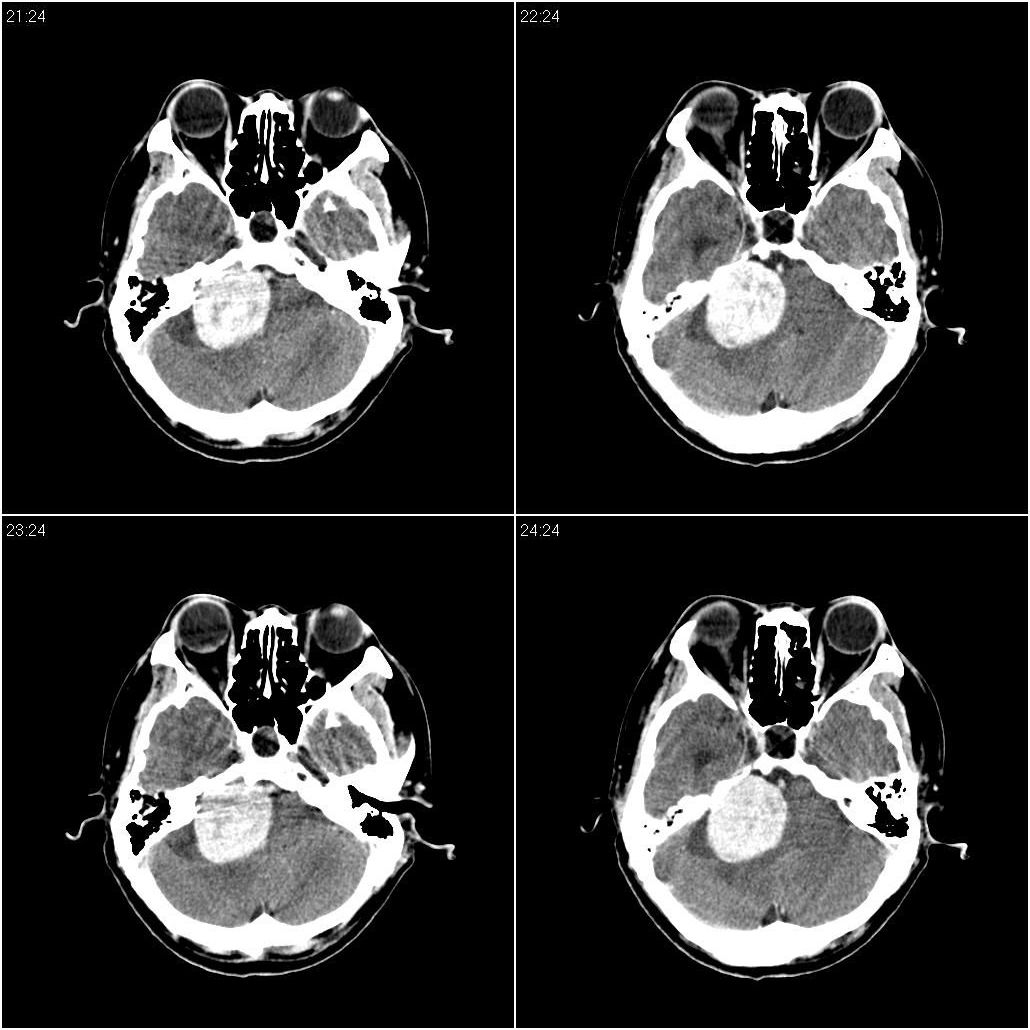

标题: CT16665:男,34岁。近来发现视力不好、眼花。 [打印本页]

标题: CT16665:男,34岁。近来发现视力不好、眼花。

考虑小脑占位性病变,建议ct增强或mri检查。

支持右侧小脑半球占位性病变伴梗阻性脑积水。建议增强,上传骨窗,除外听神经瘤

脑干密度减低,增大,与周围界限不清,四脑室受压显示不清;右侧桥小脑角区似可见稍高密度影;建议行mri检查。

看到骨窗了,右侧内听道扩大(再往下扫一层),支持听神经瘤

右侧小脑区稍低不均密度占位病变,边界不甚清楚,四脑室受压。建议ct增强或mri进一步检查。

现在有骨窗了,内听道口好像被开挖了一样,支持考虑听神经瘤先

支持幕下占位,右侧内听道扩大,听神经瘤可能,建议核磁

右侧桥小脑角区占位性病变,内听道扩大,骨质似见破坏,考虑为听神经瘤

右侧内听道扩大,支持听神经瘤

1)右侧听神经瘤。2)脑积水(梗阻性)。3)空蝶鞍。

支持:1)右侧听神经瘤。2)脑积水(梗阻性)。3)空蝶鞍。